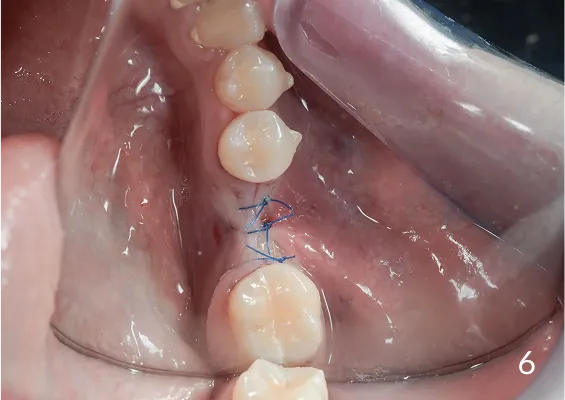

To technika pionowego rozszczepienia wyrostka zębodołowego przy użyciu osteotomów. Jest to delikatna technika zabiegowa stosowana w sytuacji braku dostatecznej ilości kości na szerokość. Polega na rozszczepieniu pionowym zanikłego w wymiarze horyzontalnym/poprzecznym wyrostka zębodołowego.

Zabiegu rozszczepienia dokonuje się przy użyciu Piezosurgery, specjalnych zestawów osteotomów lub dłut, którymi rozcina się i rozchyla kość zanikłej części zębodołowej żuchwy lub szczęk.

Pomiędzy rozchylone okładki kostne wprowadza się implanty, uzupełniając materiałem kościotwórczym pozostałą szczelinę w wyrostku. Należy w sposób właściwy dobierać i kalibrować instrumentarium, by nie spowodować uszkodzeń związanych z odłamaniem rozszczepianego fragmentu kostnego.